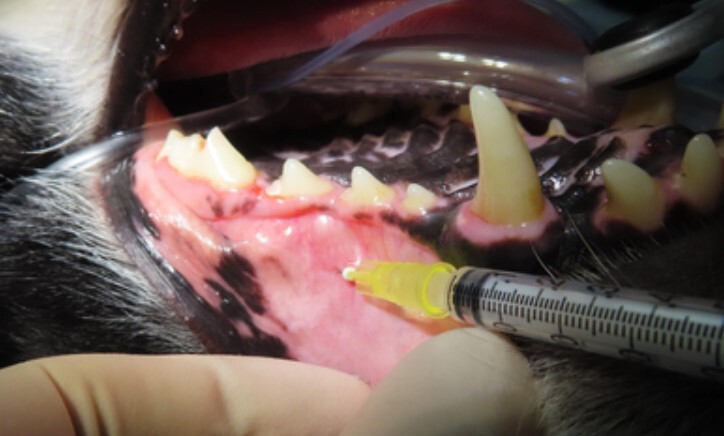

사진의 분홍색으로 보이는 부분이 신경이 노출된

골절 부위입니다.

해당 치아에 국소 마취를 적용 후 치료를 진행합니다.